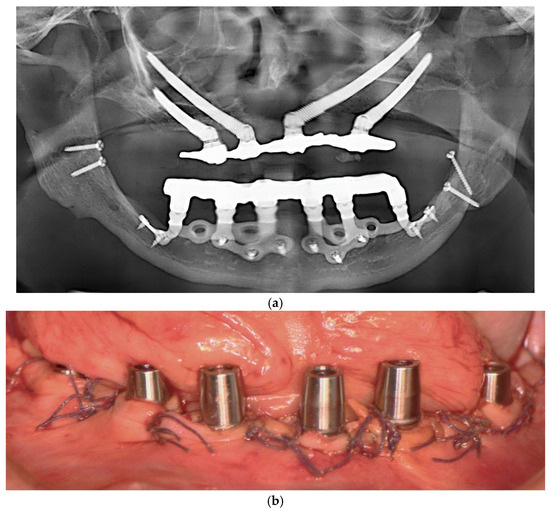

3.11. Case Series

3.11.1. Patient Demographics and Clinical Characteristics

3.11.2. Surgical and Prosthetic Protocol

3.11.3. Complications and Management

- Patient 1: Developed a localized abscess in the region of tooth 13 three months postoperatively, accompanied by soft tissue dehiscence at sites 13, 15, and 17. These were managed with local irrigation and hygiene reinforcement, with full recovery.

- Patient 2: Presented with tissue dehiscence on the lingual side.

- Patient 3: Presented with tissue dehiscence around the second abutment of the upper left implant. The condition was resolved through improved oral hygiene.

- Full-thickness flap elevation with identification of vital structures. (Prevents nerve injury and ensures proper implant bed access).

- Minimal osteoplasty when needed for passive fit. (Improves implant adaptation to the bony surface).

- Fixation with titanium screws at preplanned anchorage points. (Provides mechanical stability without intraosseous engagement).

- Strict aseptic handling of the implant. (Reduces risk of postoperative contamination).